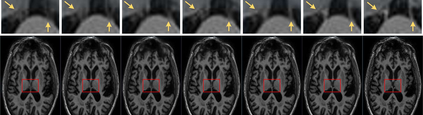

The thick-slice magnetic resonance (MR) images are often structurally blurred in coronal and sagittal views, which causes harm to diagnosis and image post-processing. Deep learning (DL) has shown great potential to re-construct the high-resolution (HR) thin-slice MR images from those low-resolution (LR) cases, which we refer to as the slice interpolation task in this work. However, since it is generally difficult to sample abundant paired LR-HR MR images, the classical fully supervised DL-based models cannot be effectively trained to get robust performance. To this end, we propose a novel Two-stage Self-supervised Cycle-consistency Network (TSCNet) for MR slice interpolation, in which a two-stage self-supervised learning (SSL) strategy is developed for unsupervised DL network training. The paired LR-HR images are synthesized along the sagittal and coronal directions of input LR images for network pretraining in the first-stage SSL, and then a cyclic in-terpolation procedure based on triplet axial slices is designed in the second-stage SSL for further refinement. More training samples with rich contexts along all directions are exploited as guidance to guarantee the improved in-terpolation performance. Moreover, a new cycle-consistency constraint is proposed to supervise this cyclic procedure, which encourages the network to reconstruct more realistic HR images. The experimental results on a real MRI dataset indicate that TSCNet achieves superior performance over the conventional and other SSL-based algorithms, and obtains competitive quali-tative and quantitative results compared with the fully supervised algorithm.